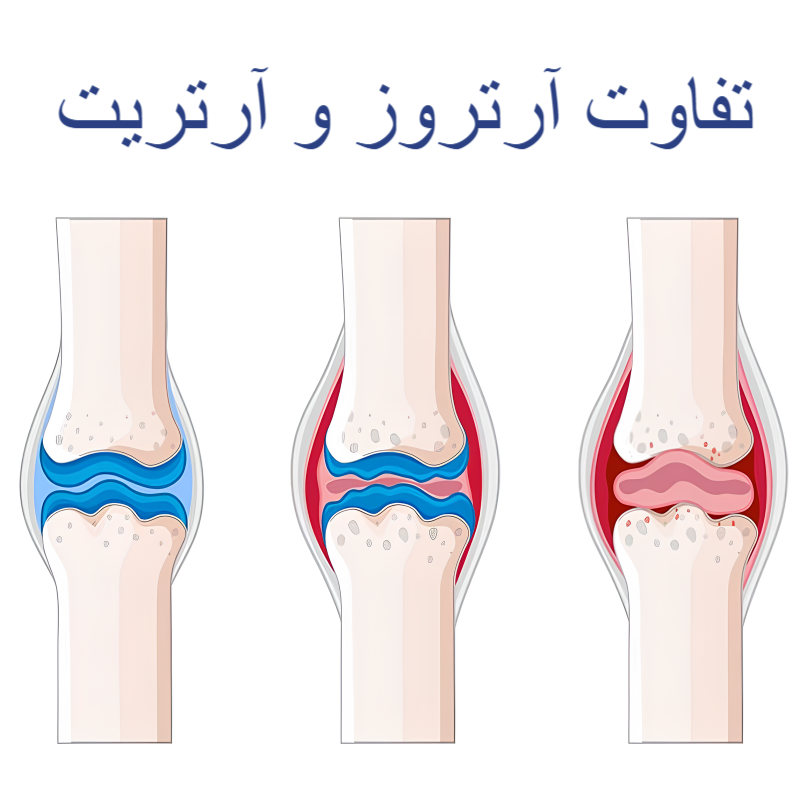

اگرچه آرتروز و آرتریت دو بیماری مرتبط با مفاصل هستند ولی در پاسخ به سوال فرق آرتروز و آرتریت چیست؟ باید گفت که در واقعیت این ها دو تا بیماری متفاوت هستند. که در ادامه توضیح می دهیم.

فرق آرتروز و آرتریت چیست؟

آرتریت یک اصطلاح کلی برای بیماری های التهابی مفصل است و بیش از صد نوع مختلف را در بر می گیرد. این گروه از بیماری ها می توانند علل متفاوتی مانند اختلالات خودایمنی، عفونت ها یا مشکلات متابولیک داشته باشند و معمولاً با علائمی مثل درد، تورم، گرمی، قرمزی مفصل و خشکی طولانی مدت صبحگاهی همراه هستند. آرتریت میتواند چندین مفصل را به طور همزمان درگیر کند و در هر سنی دیده شود.

در مقابل، آرتروز یا استئوآرتریت شایع ترین نوع آرتریت و یک بیماری غیر التهابی و سایشی مفصل محسوب می شود. در این بیماری، غضروف مفصل به تدریج تخریب می شود که نتیجه آن کاهش حرکت مفصل، درد و گاهی تغییر شکل مفصل است. آرتروز بیشتر در سنین بالا بروز می کند و مفاصلی مانند زانو، لگن، ستون فقرات و انگشتان را درگیر می سازد.

درد در آرتروز معمولاً با فعالیت تشدید شده و با استراحت کاهش می یابد و خشکی صبحگاهی آن کوتاه مدت است. برخلاف بیشتر انواع آرتریت، در آرتروز علائم واضح التهاب مانند قرمزی و گرمی شدید کمتر دیده می شود و مدیریت بیماری بیشتر بر اصلاح سبک زندگی، تقویت عضلات، کاهش وزن و کنترل درد تمرکز دارد.